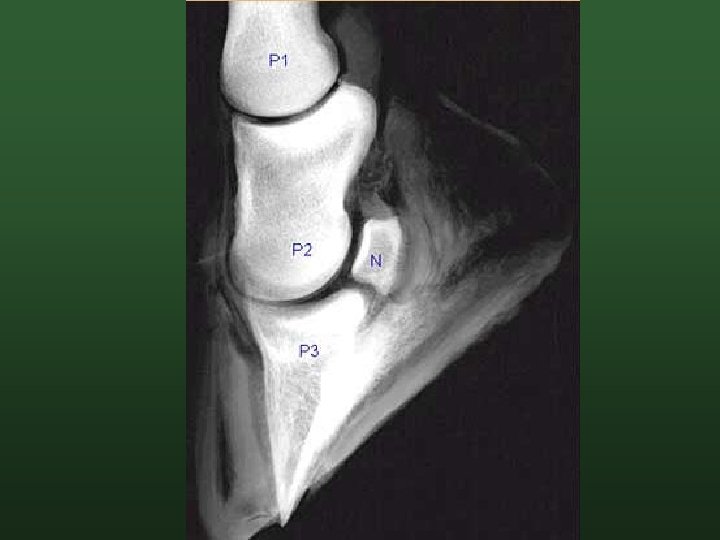

Bovine Suspensory Apparatus P 3 fixed supported by digital cushion and suspended by bundles of collagen fibers attached to the basement layer of the abaxial wall. If fibers stretch P 3 sinks and Deforms and compresses the sole. From Lischer & Ossent, 2007

Effects of Laminitis and Sinkage of P 3 on the Digital Cushion From Lischer & Ossent, 2007.